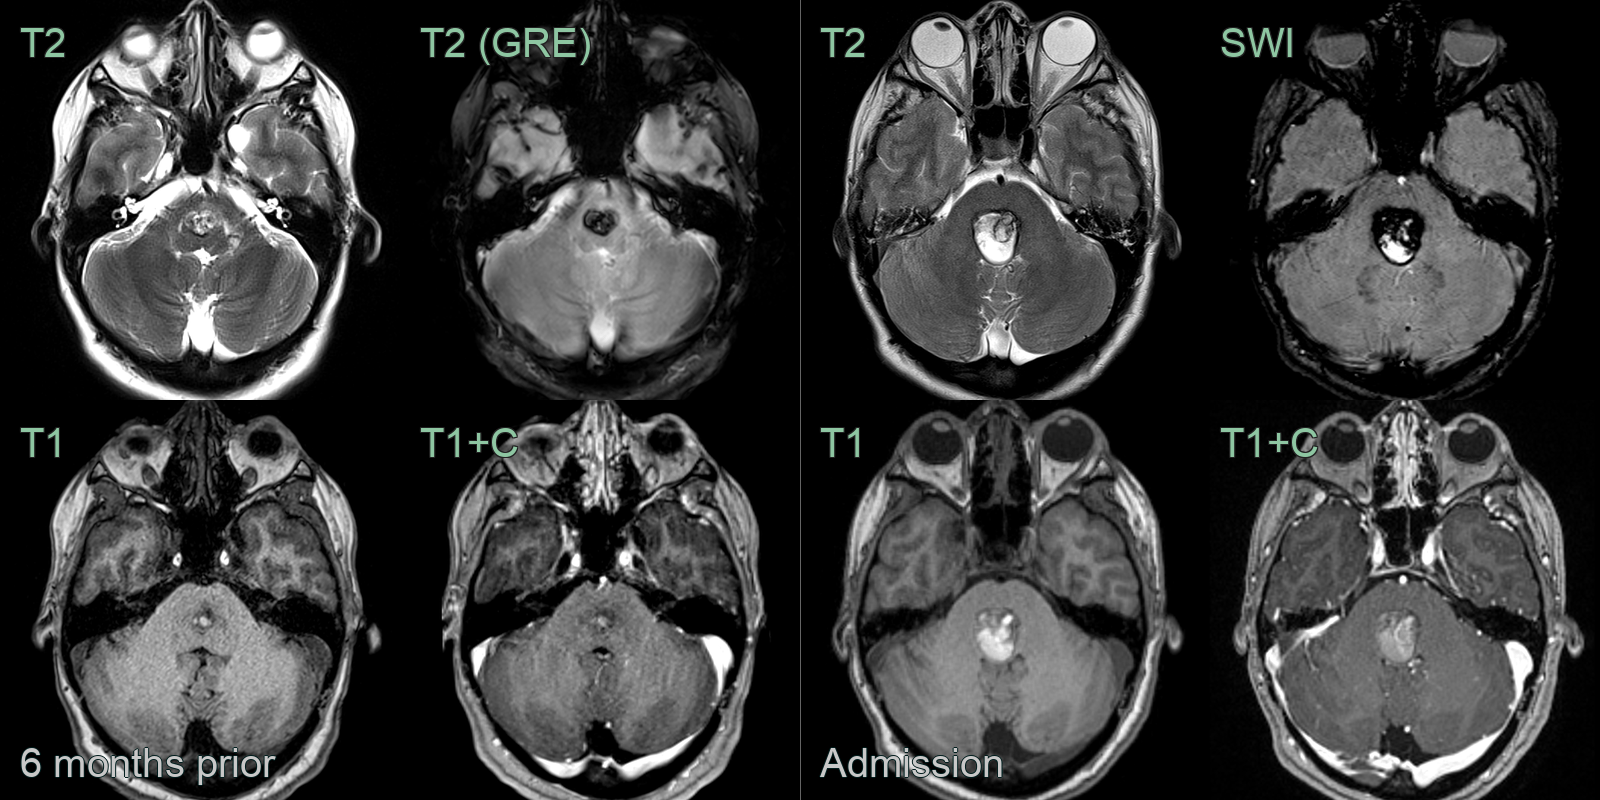

- A 40-year-old patient presented 2 years prior with headache.

- Initial imaging (not shown) showed a hematoma in the left insular region.

- MRI showed many other low intensity lesions within the brain and cervical cord representing cavernomas.

- The T1-shortening within the frontal operculum represented evolving blood product from the hemorrhage at presentation.